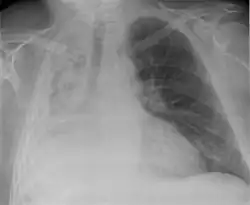

Hemothorax

Hemothorax, or accumulation of blood in the pleural space, can result from trauma or surgical procedures in the chest. This accumulation of blood can grow large enough to compress the lung and push away other structures in the chest, thus causing a mediastinal shift.[6] On a chest x-ray, a hemothorax can appear similarly to a pleural effusion with blunting of the pleural recess and white out of normal lung zones.[7] In the setting of traumatic chest injury, rib fractures are also commonly observed on x-ray.[8]